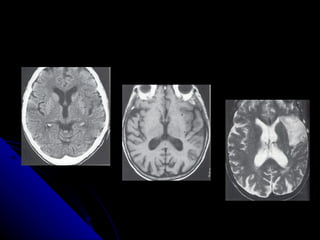

CAUSAS DE AFASIA 1.- infartos y hemorragias 2.- Neoplasias primarias o metastasicas 3.- demencias Pick y Alzheimer 4.- lesiones traumáticas

CAUSAS DE AFASIA1.- infartos y hemorragias 2.- Neoplasias primarias o metastasicas 3.- demencias Pick y Alzheimer 4.- lesiones traumáticas